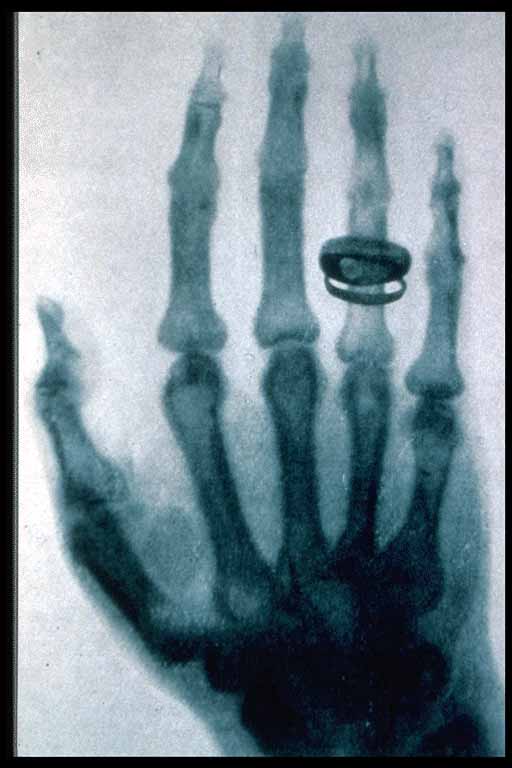

X-rays are extremely short wavelength -- a thousand times shorter than visible light. This means they are also very high frequency. X-rays can penetrate matter because they are so high frequency that the atoms cannot respond very much.

Xrays can go through flesh but are slightly absorbed by bones. This photograph reveals the bones in a man's hand (as well as his ring), as shadows.

Reprinted with permission of the American College of Radiology, Reston, Virginia. No other representation of this material is authorized without express, written permission from the American College of Radiology